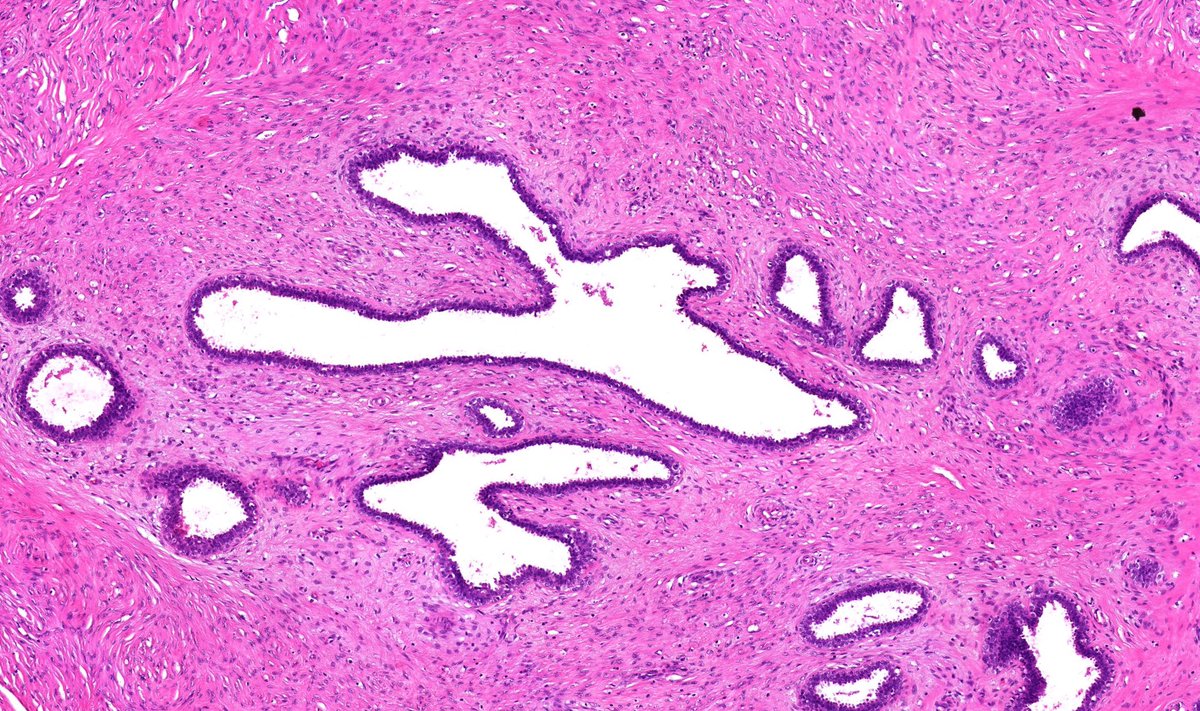

Fibroadenoma

1/ Original thought to arise from ectopic breast tissue, it is now thought they arise from anogenital mammary-like glands (which are normal structures).

2/ Other lesions such as hidradenoma papilliferum are thought to arise from these.